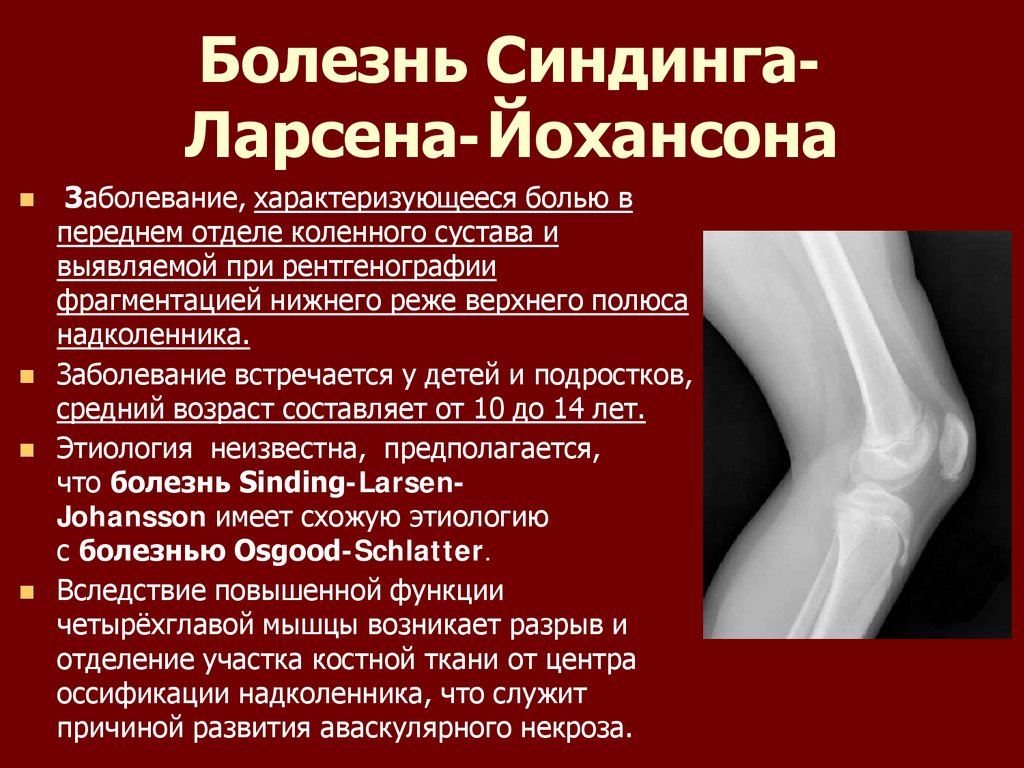

Ларсена йохансона

Ларсена йохансона 146 фото